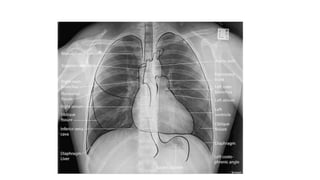

This document discusses key aspects of thorax radiology including positioning for PA and AP views, assessing heart size, visibility of anatomical structures like the scapulae, lungs zones, and measurements like cardiothoracic ratio. It provides guidance on evaluating rotation, inspiration, and penetration on chest x-rays as well as identifying structures like the lobe of azygos vein and aortic knuckle.